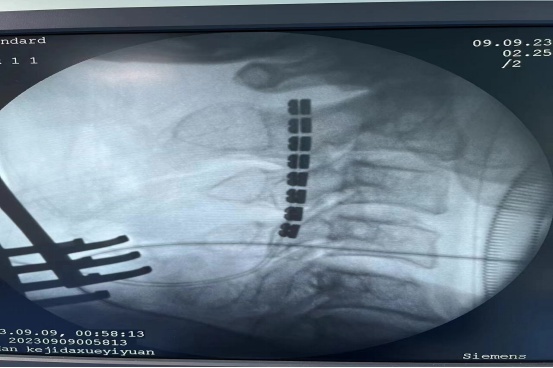

术中透视显示电极位置正常。

12月11日,杨学带领神经外科医护团队行脊髓电刺激术,术后根据陈爷爷反应情况设置个体化的刺激强度。“促醒手术会给昏迷不醒的患者带来苏醒希望,通常术后苏醒到逐渐好转需要一段漫长的时间。”杨学介绍,脊髓电刺激术对于治疗意识障碍具有一定的疗效,不过,促醒手术也有时间窗,一般在慢性意识障碍超过3月,生命体征稳定,经高压氧及常规康复治疗后,意识水平达到微意识状态的患者;无神经退行性疾病(阿尔茨海默等)或消耗性疾病(肿瘤、恶病质)导致的昏迷等类型的患者可考虑行脊髓电刺激术。据统计,经过筛选后的微小意识状态患者,手术促醒率可达到30%—50%。

杨学带领神经外科医护团队为陈爷爷行“脊髓电刺激术”。